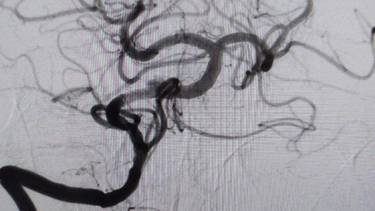

Фото: Министерство здравоохранения Московской области

Врачи Мытищинской больницы спасли 48-летнего мужчину с редкой и опасной формой «ночного» инсульта. Об этом в среду, 19 ноября, сообщили в пресс-службе Министерства здравоохранения Московской области.

В ведомстве рассказали, что пациент несколько месяцев испытывал недомогание и однажды утром не смог встать с кровати. Врачи диагностировали «ночной» инсульт, который часто маскируется под легкие симптомы. У пациента не было паралича, он мог двигать руками и ногами, а речь оставалась внятной.

— У пациента был выявлен атеротромбоз — тромбоз на фоне атеросклеротической бляшки — основной артерии, которая обеспечивает кровоснабжение важнейших отделов головного мозга. Это очень тяжелое состояние с крайне высокой летальностью. К счастью, мы успели вовремя, и операция прошла успешно, — рассказала заведующая больницей Элеонора Тулякова.

После лечения мужчину выписали на амбулаторное лечение, на данный момент он чувствует себя лучше, передает сайт Минздрава.